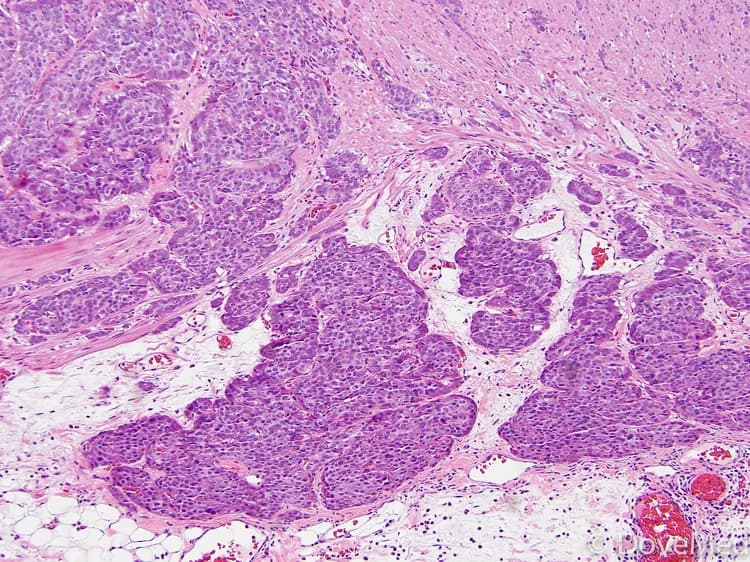

• Carcinoid Tumors of Lung are uncommon neuroendocrine tumors that constitute 2 main types - typical carcinoid and atypical carcinoid tumors. The tumors are identified on histological examination of a tumor sample by a pathologist under a microscope

• A biopsy of the tumor is performed and sent to a laboratory for a pathological examination. A pathologist examines the biopsy under a microscope. After putting together clinical findings, special studies on tissues (if needed) and with microscope findings, the pathologist arrives at a definitive diagnosis. Examination of the biopsy under a microscope by a pathologist is considered to be gold standard in arriving at a conclusive diagnosis

• Biopsy specimens are studied initially using Hematoxylin and Eosin staining. The pathologist then decides on additional studies depending on the clinical situation

• Sometimes, the pathologist may perform special studies, which may include immunohistochemical stains, molecular testing, flow cytometric analysis and very rarely, electron microscopic studies, to assist in the diagnosis